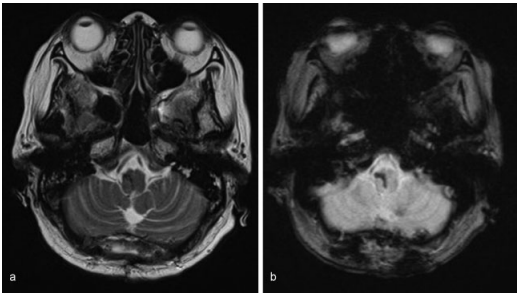

图:磁共振图像显示出血没有明显的病理原因,(a)T2加权(b)T2加权。

因此,她在入院后3天进行开颅手术。在右侧延髓观察到血肿,并通过冲洗清除血肿。血肿清除后,延髓肿胀减轻。术中神经生理监测(运动诱发电位和感觉诱发电位)保持不变。术中无海绵状畸形等病理学证据。术后CT显示血肿消失。

手术后,她的自主呼吸提高到每分钟15次以上。术后第5天停止呼吸机支持,术后第6天拔管。术后5周核磁共振成像显示无结构异常。康复后,自主步行出院,没有进一步的并发症。